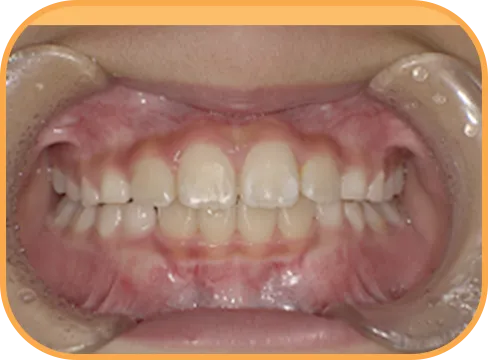

• Before

• 正 面

治療前正面からの歯の様子

• 上 顎

治療前上顎からの歯の様子

• 下 顎

治療前下顎からの歯の様子

• 右 側

治療前右側からの歯の様子

• 左 側

治療前左側からの歯の様子

主 訴

前歯が開いている

治療内容

インビザライン・ファースト

治療期間

6か月

治療費(税別)

450,000円+診断料30,000円

リスク・副作用

• 親知らずの影響や加齢などによって、凸凹が生じる可能性があります。

• 治療の初期段階では痛みや不快感が生じやすくなりますが、1週間前後で慣れます。

• 顎の成長発育によって、噛み合わせや歯並びが変化する可能性があります。

• 状況により当初予定した治療計画を変更する可能性があります。